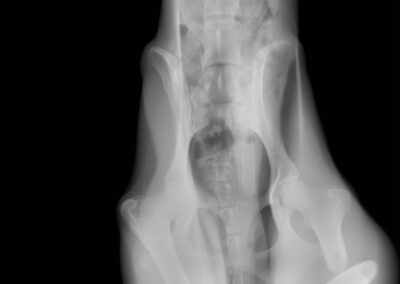

Marcus n’était plus qu’un véritable squelette, avec une fracture complexe du fémur au postérieur gauche. Il a dû vivre un véritable enfer, seul, blessé et affamé…

Il a été opéré en urgence à la clinique du refuge de la FBM, où il est actuellement en convalescence 🩺. La clinique est aujourd’hui totalement saturée, faisant face chaque jour à l’arrivée de nouveaux cas lourds : fractures, blessures graves, chiens brisés par la maltraitance et l’abandon… 😞 Malgré cette situation extrêmement difficile, Marcus a pu être pris en charge et bénéficie désormais de tous les soins nécessaires.